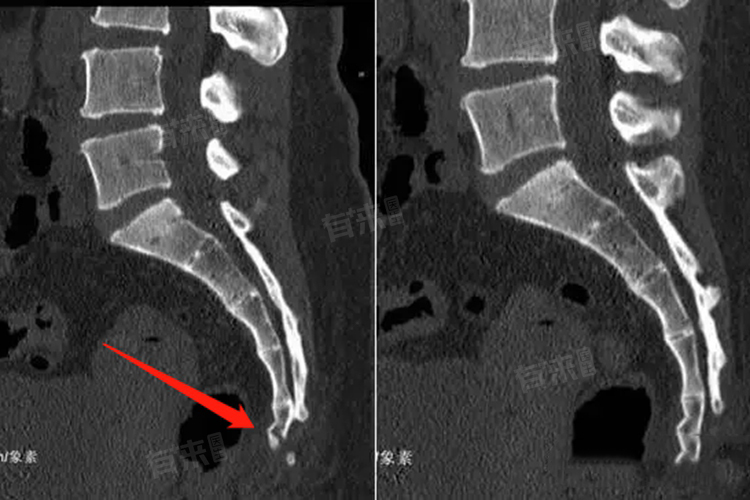

- 切开复位内固定术:适用于骨折移位明显、不稳定的骶椎骨折,或伴有神经损伤的情况。通过手术切开暴露骨折部位,将骨折端复位并用钢板、螺钉等内固定物进行固定,以恢复骶椎的解剖结构和稳定性,为骨折愈合创造良好条件,同时解除对神经的压迫。

- 骶骨重建术:对于严重粉碎性骶椎骨折,可能需要进行骶骨重建术,使用人工骨或自体骨移植等方法修复受损的骶骨,恢复其支撑和保护功能。